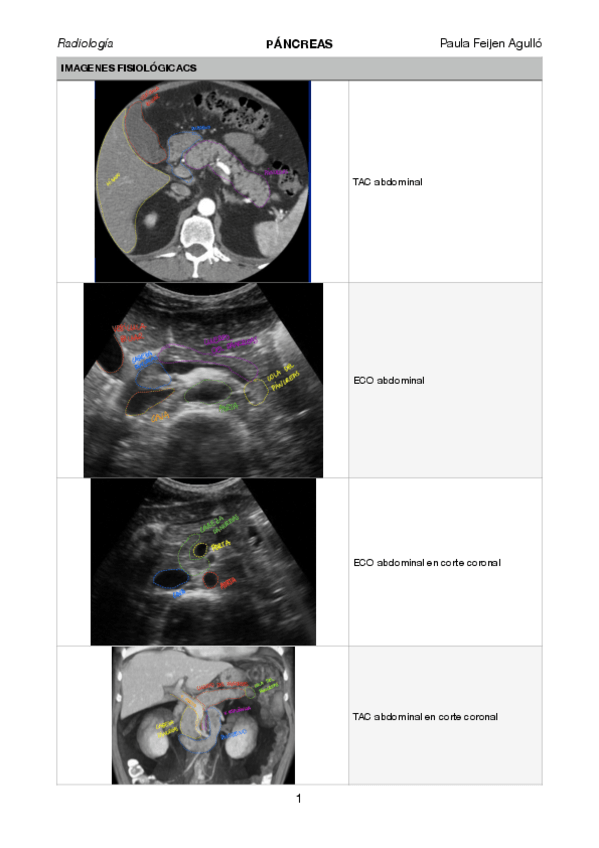

pancreas.pdf